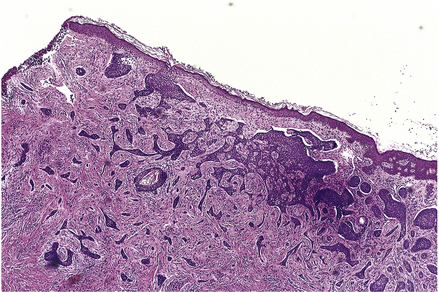

Lichen planus

image Polygonal, itchy papules

image Band-like chronic inflammatory infiltrate

image Centred on dermo-epidermal junction

Lichen planus is a non-infectious inflammatory disease characterised by destruction of keratinocytes, probably mediated by interferon-gamma and tumour necrosis factor from T-cells in the dermal infiltrate. Usually there is no precipitating factor but some drug eruptions may be indistinguishable. It affects the skin, often the inner surfaces of the wrists (Fig. 24.8), and the mucosae, where it appears as a white lacy lesion. On the skin it presents as small, intensely itchy, polygonal, violaceous papules that may develop into blisters, particularly on the palms of the hands or soles of the feet. As the eruption heals, which it usually does spontaneously, it may leave behind hyper- or hypopigmented patches.

Clinicopathological features

Histology reveals a lymphohistiocytic infiltrate in a band-like distribution at the dermo-epidermal junction. The basal layer of the epidermis comes under lymphocytic attack and foci of degeneration, apoptosis and regeneration are seen; this eventually gives the epidermis a characteristic saw-tooth profile. Little splits also occur at the junction and, rarely, these may coalesce to form bullae (Fig. 24.9). Lichen planus constitutes the classical so-called lichenoid reaction. In contrast to psoriasis there is an increase in the granular layer; the scale is consequently different and presents as tiny white lines running over the papules. During the active phase of the eruption papules can be induced by minor trauma such as scratching. Treatment is with steroids, and in those cases in which a precipitating cause can be identified this can then be withdrawn.

image

Fig. 24.9 Lichen planus. An inflammatory skin disease of unknown aetiology. The progression from normal skin to healed lesion is shown diagrammatically from left to right.